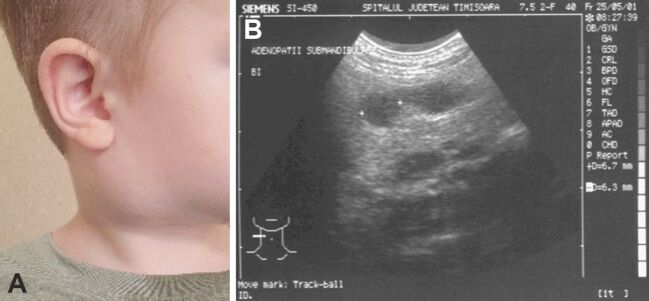

The discovery of a cervical mass in children is a situation quite frequently encountered and often represents a diagnostic or therapeutic challenge for the practicing physician. Although approximately 12% to 15% of all neck masses (NMs) in children may be malignant, most commonly these masses are benign. This study included 137 patients aged between 14 months and 18 years old, with the majority (54.01%) of patients being less than five years old. A total of 83 (60.58%) patients were presented with a single NM, with 64 (59.12%) patients having mass located on the midline of the neck. Preoperatively, in addition to laboratory tests, imaging examinations played an important role in diagnostic orientation and determining the therapeutic plan. Among the imaging examinations, ultrasound was the most commonly used, performed in 87 (63.5%) of the patients. The definitive diagnosis was established based on the histopathological examination of the excised specimens. Midline NMs were most frequently thyroglossal duct cysts or dermoid cysts, while lateral NMs were often lymphadenitis or branchial cysts. The aim of this study was to present the experience of 10 years in evaluating cervical masses in the neck area that appeared in children, their possible causes, the methods of investigation (considering the contribution and limitations of each diagnostic method), and the therapeutic approach (since there is no clear standardization of treatment in the literature).